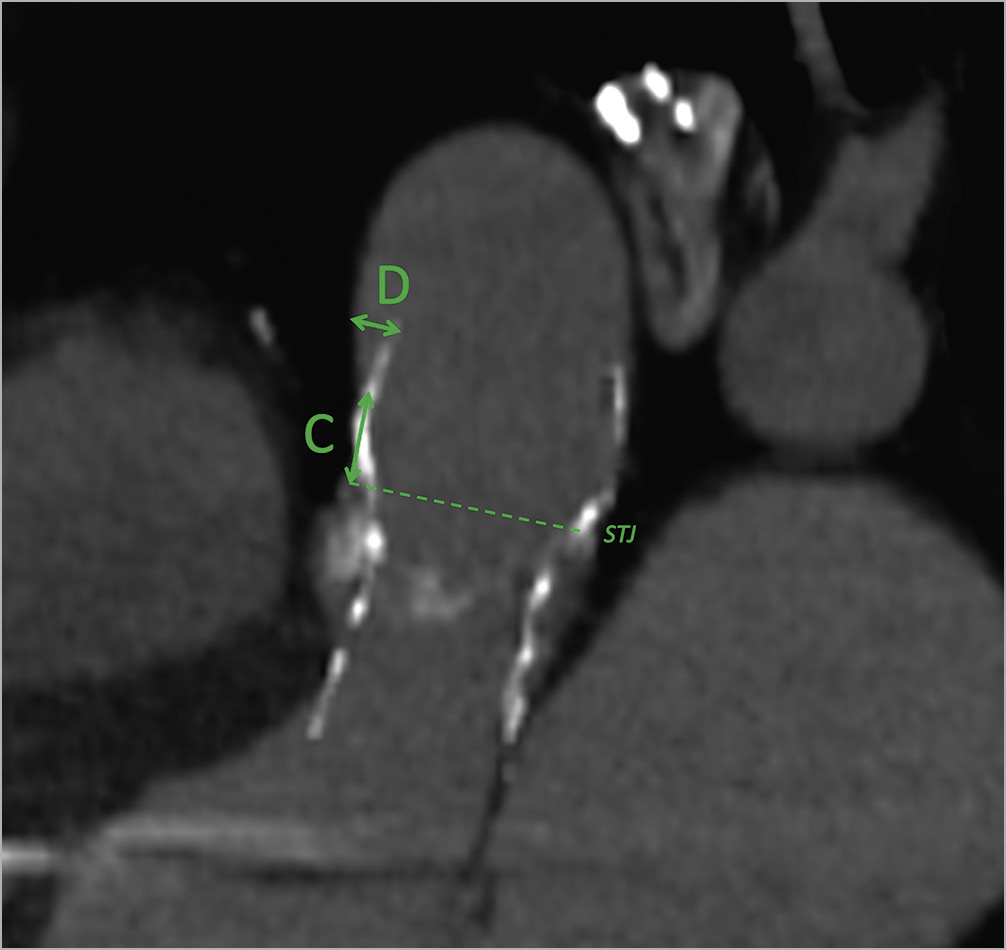

Four principal measurements were evaluated (Table 1): 1) the shortest distance between the THV and the most inferior point of the innominate artery (Figure 1, green A); 2) the shortest distance between the centre of the virtual basal ring (VBR) and the most inferior point of the innominate artery ostium (Figure 1, green B); 3) the minimal distance between the sinotubular junction (STJ) and the first THV-free anterior aortic wall point (Figure 2, green C); and 4) the maximum gap between the anterior ascending aortic wall and the upper margin of the THV stent frame (Figure 2, green D). The aim of analysing these specific measures relies mostly on two aspects, for A+B and C+D distances, respectively: first, of having enough comfort space for the positioning of the surgical ascending aortic clamp, avoiding the innominate artery ostium and the THV stent below the aortic wall; and second, of performing a safe aortotomy by scalpel without the risk of becoming entangled with the TAVI upper stent.

Figure 2. CT-scan reconstruction showing measures for aortotomy. Post-TAVI CT-scan reconstruction, oblique-sagittal view (sternum on the left of the image), showing the measures for an adequate aortotomy: the minimal distance between the STJ and the THV-free anterior aortic wall point (green C); and the maximum gap between the anterior ascending aortic wall and the upper margin of the THV stent (green D). CT: computed tomography; STJ: sinotubular junction; TAVI: transcatheter aortic valve implantation; THV: transcatheter heart valve